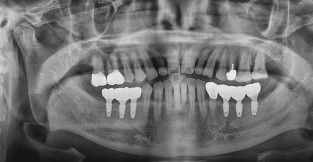

• 3

상악동거상술 임플란트

치료기간 : 2024-06-24 ~ 2024-11-22

1. 상기 x-ray 이미지 모두 동일한 해당 의료기관에서 진료한 환자입니다.

2. 상기 x-ray 이미지 모두 동일 인물의 것입니다.

3. 치료 전 이미지는 2024-06-24에 촬영했으며, 치료 후 이미지는 2024-11-22에 촬영하였습니다.

4. 상기 x-ray 이미지 모두 동일 조건에서 환자분의 동의를 받아촬영되었습니다.

* 임플란트 시술은 환자분의 상태(고혈압, 당뇨 등)에 따라 부작용이 있을 수 있으니, 반드시 전문의와 상담이 필요합니다.

* 임플란트 수술 부작용

: 수술 후 출혈, 교합, 통증, 붓기, 염증 등의 문제점이 발생할 수 있습니다.)